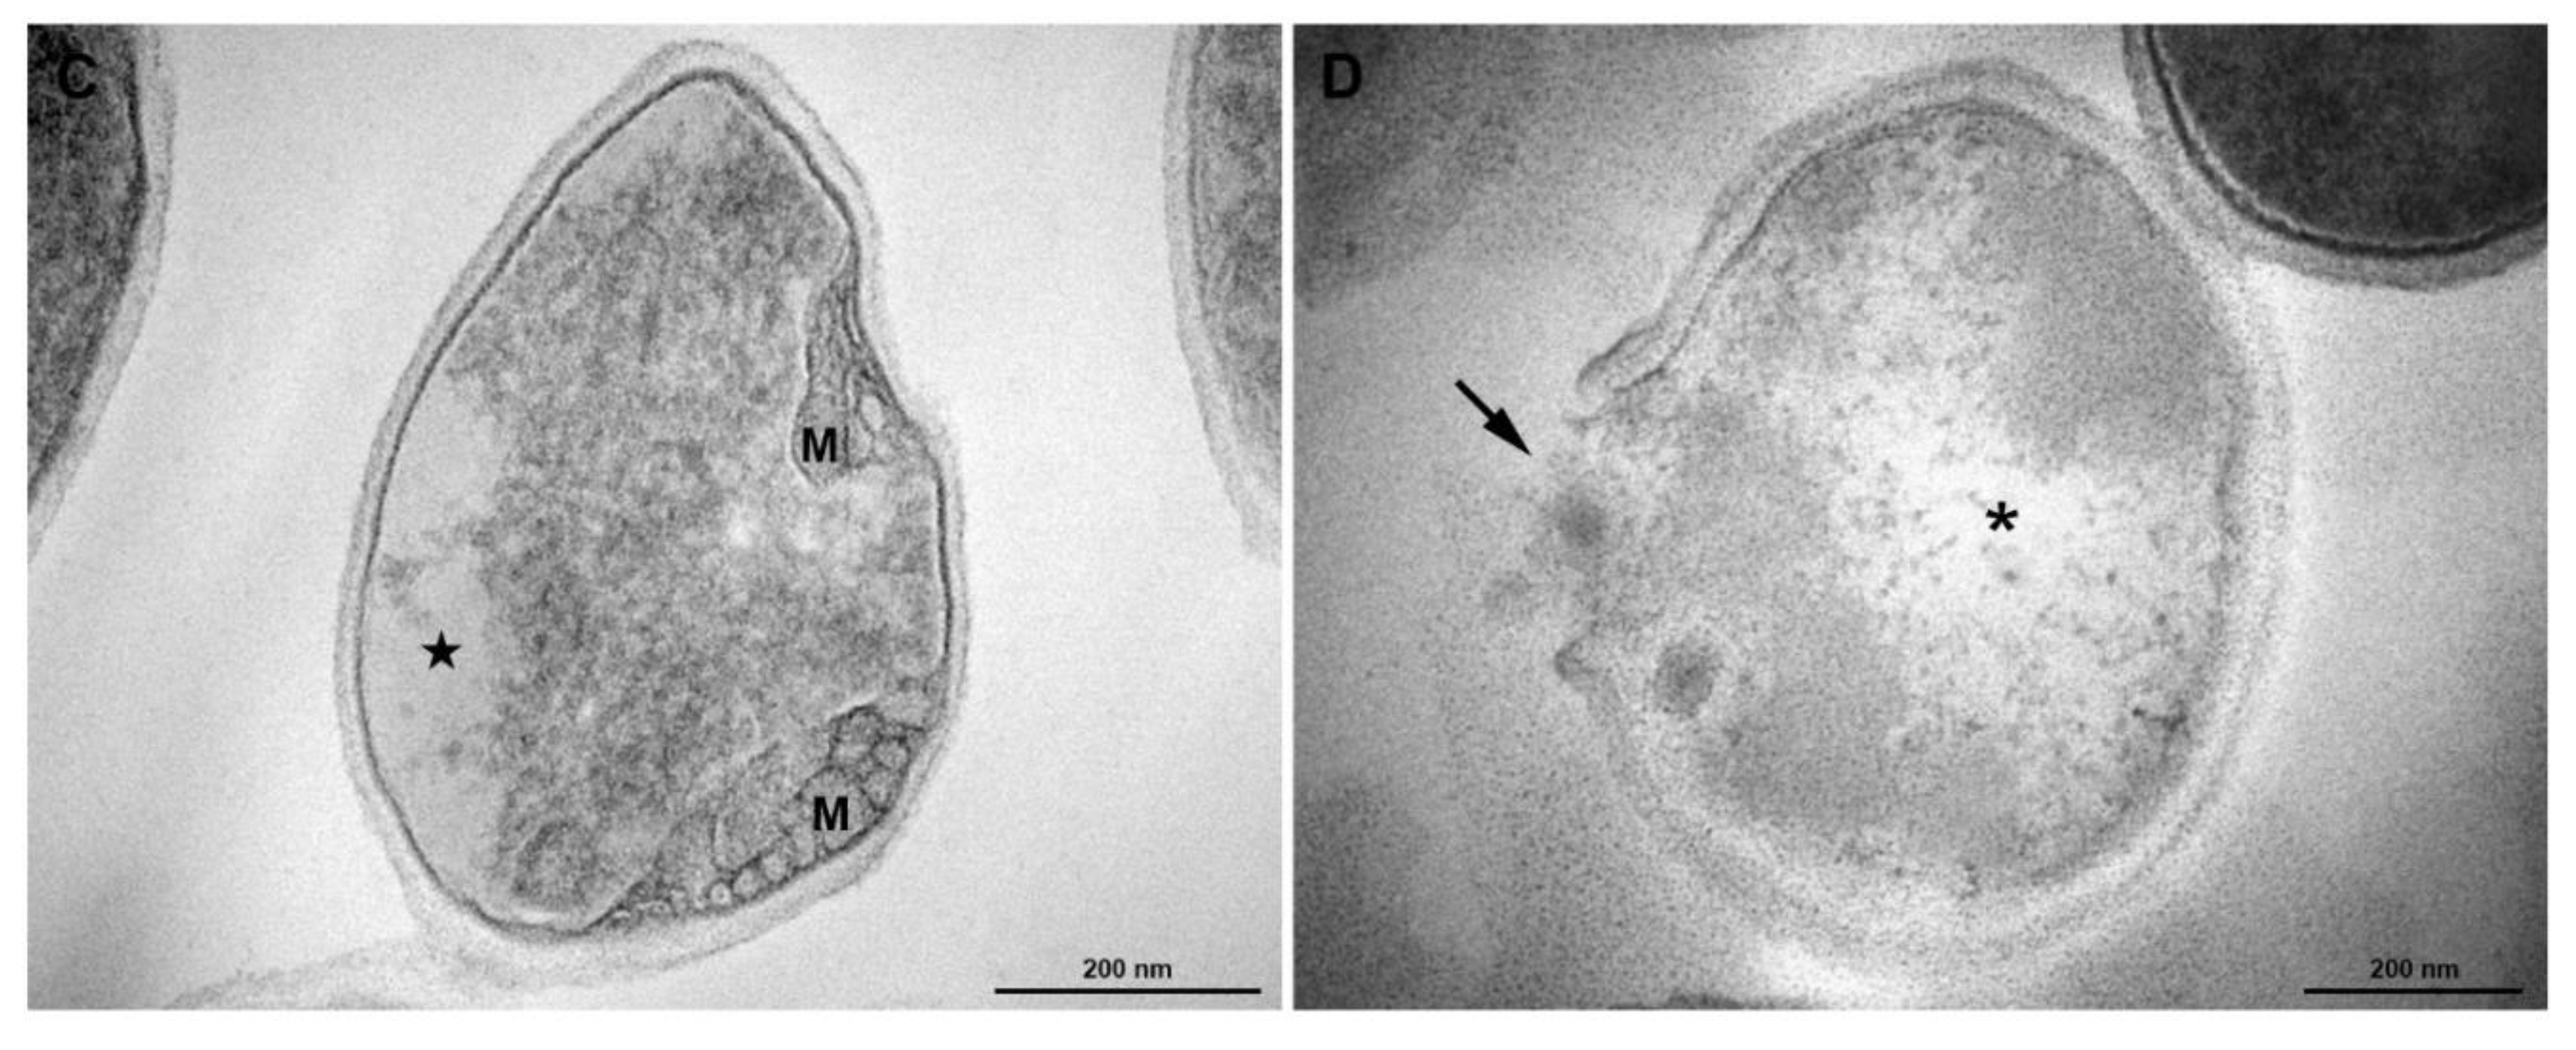

3.5. Transmission Electronic Microscopy